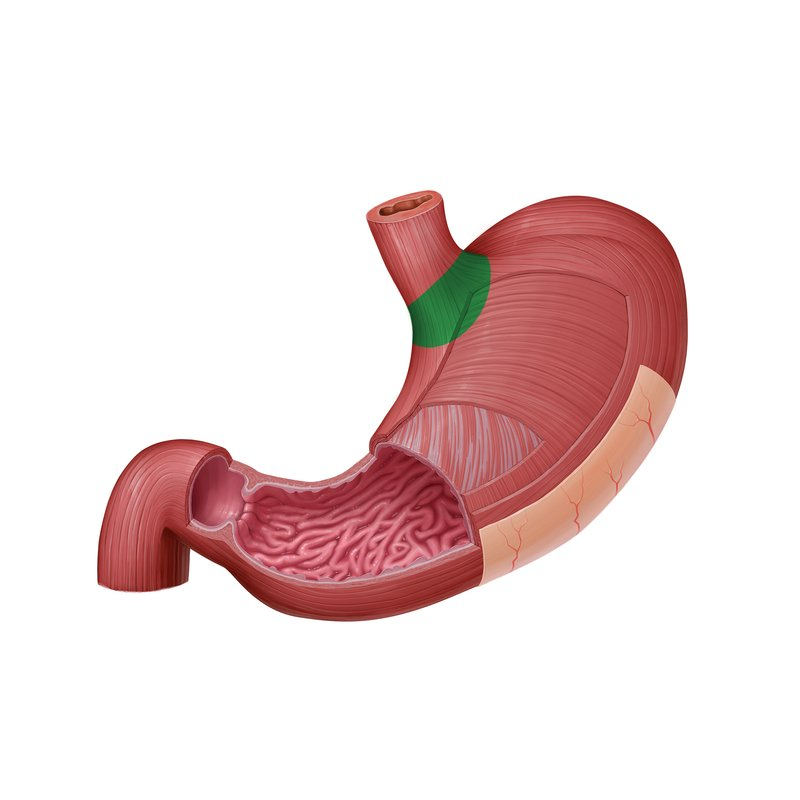

Stomach

a J-shaped organ located in the upper abdomen that stores, mixes, and digests food.

Lower esophageal sphincter

A muscular ring located at the junction of the esophagus and the stomach that controls the passage of food into the stomach and prevents reflux of stomach contents back into the esophagus

Body of stomach

the main, central part of the stomach.

Cardia

The region of the stomach where the esophagus joins.

Fundus

The dome-shaped, upper portion of the stomach that lies superior to the esophageal opening.

Rugae

folds in the lining of the stomach that allow for expansion when the stomach is filled with food.

lesser curvature

the concave medial border of the stomach.

Pyloric sphincter

A muscular ring located at the junction of the stomach and the duodenum (the first part of the small intestine) that controls the emptying of stomach contents into the duodenum.

Pyloric canal

the narrow passageway that leads from the pyloric antrum to the pyloric sphincter.

Pyloric antrum

The funnel-shaped region of the stomach that precedes the pyloric canal.

Pylorus

The distal, narrow region of the stomach that connects to the duodenum, including the pyloric antrum, pyloric canal, and pyloric sphincter.